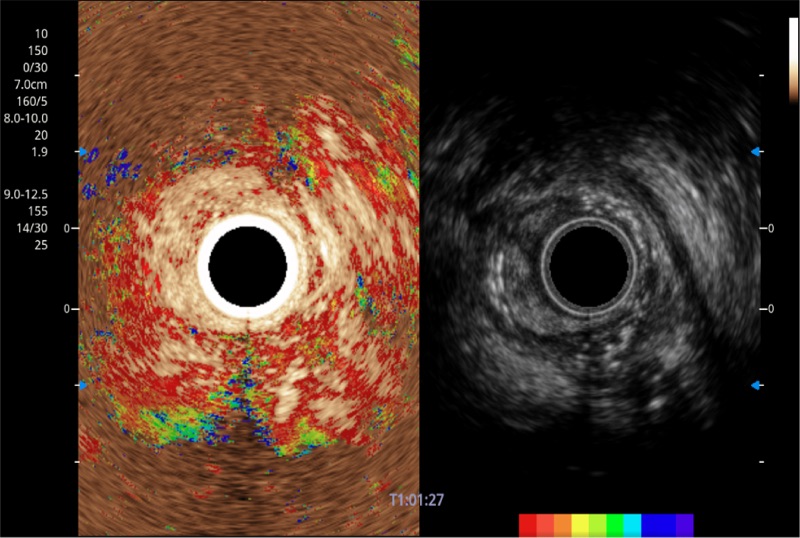

清晰显示胆总管及周围血管分布